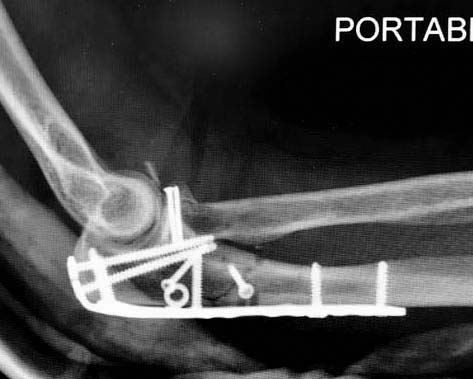

А так, здесь имеется многофрагментарный проксимальный перелом локтевого отростка с переломо-вывихом головки лучевой кости по классификации Mason III. Решение принимается на основании КТ срезов, потому что на боковом рентген снимке вроде отсутствует смещение, где сустав и контур Coronoid в одном блоке, а на прямом подозрение на смещение в Coronoid?

Для перелома локтевого отростка придуманы много пластин, надо выбрать по длине. А при краевых переломах головки ее окружность можно восстановить винтами 2 мм, но в данном случае имеется полный вывих головки и фиксация, даже специальной пластиной, может осложнится. Протез головки после удаления предупреждает нестабильность в суставе и деформацию оси конечности в будущем!

Конверсионные спицы на уровне проксимального отдела лучевой кости интересная идея, но на уровне перелома в области шейки трудно удержать головку. Предварительная репозиция локтевого отростка с временной установкой пластины, затем удаление экономит время. Доступ через локтевой отросток, где можно фиксировать или удалить головку с замещением, а потом установить пластину обратно на локтевой отросток!